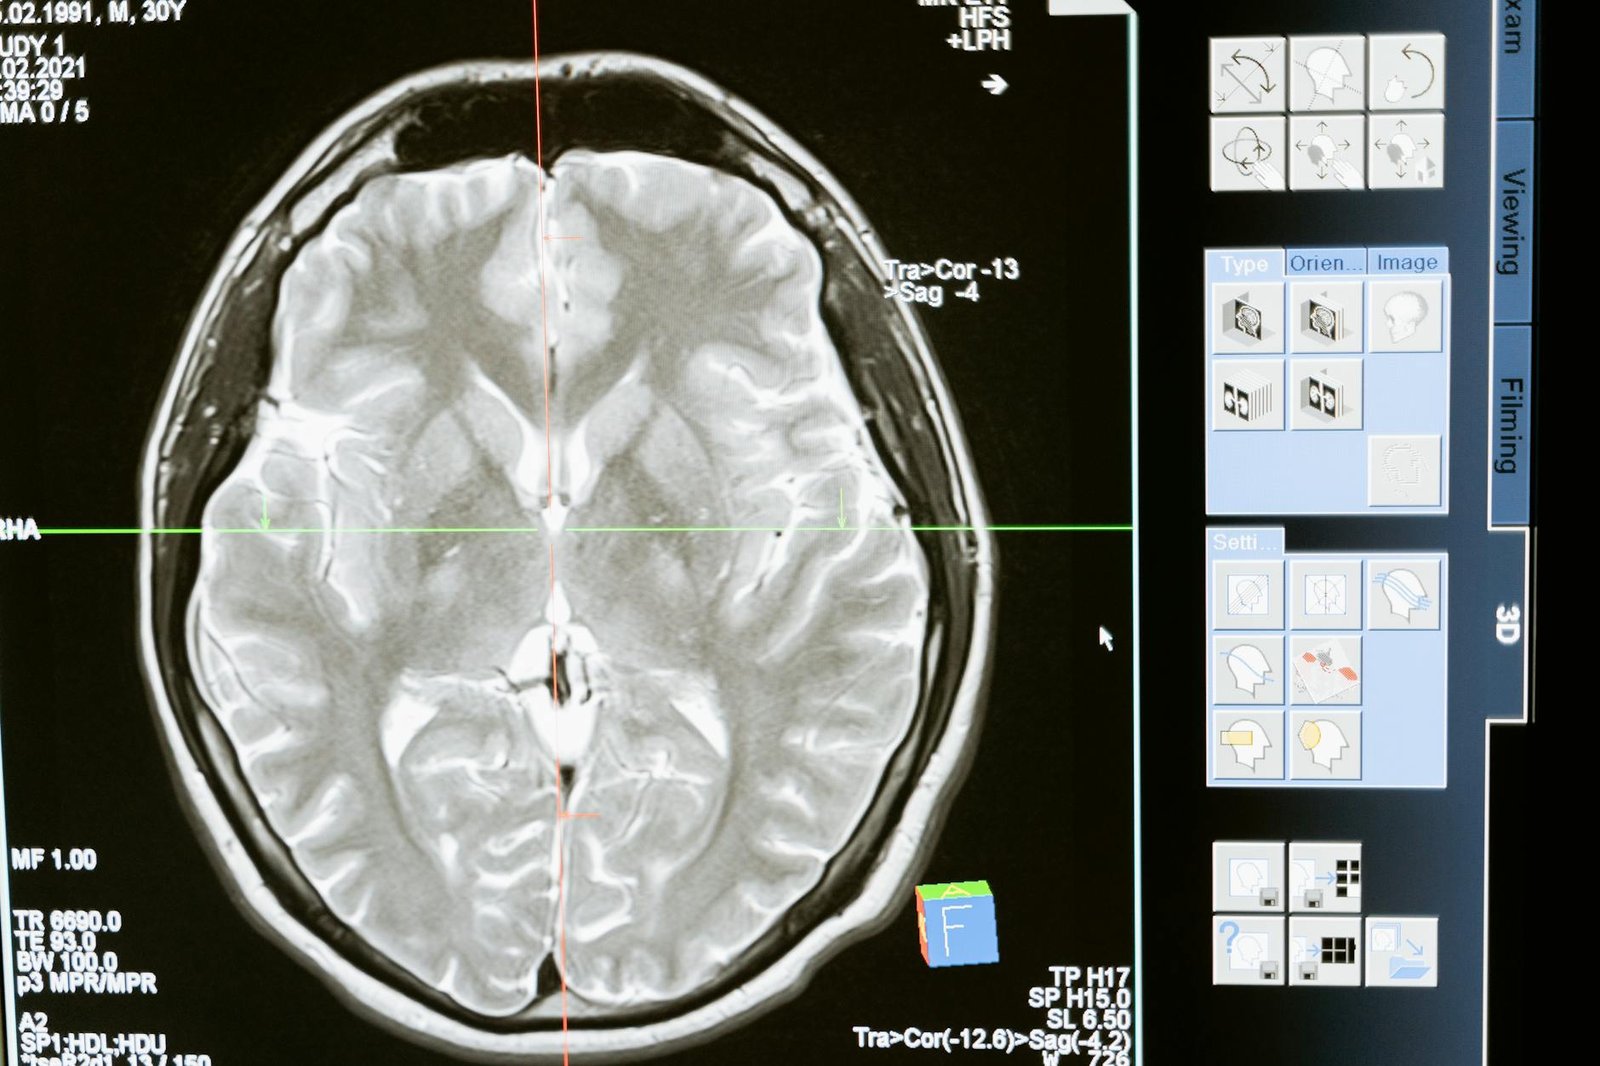

Photo by MART PRODUCTION on <a href="https://www.pexels.com/photo/technology-computer-head-health-7089020/" rel="nofollow">Pexels.com</a>